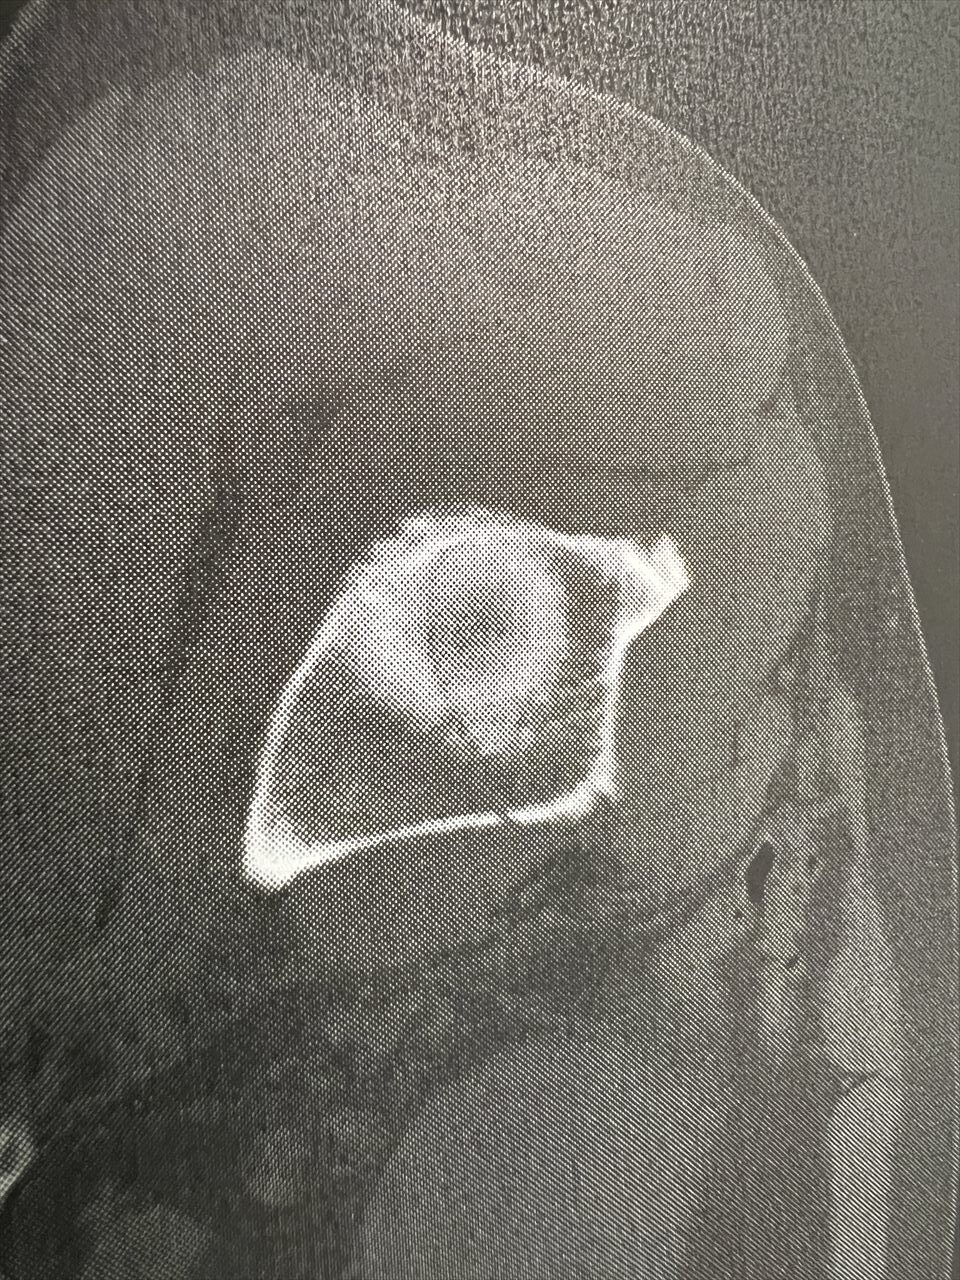

2ヶ月の長きに亘る入院生活も終わりを告げます。骨盤の骨折部分も概ね修復されました。CT写真のとおりです。

最初は、くっきりとスジが見えましたが、だんだんとぼけていき、最終的には、スジが見えなくなってきましたね。

8月9日は、はっきりとエッジのある亀裂が認められるが、10月9日は、完全にぼやけていて、亀裂が不明瞭。すなわち、亀裂がふさがったということですね。